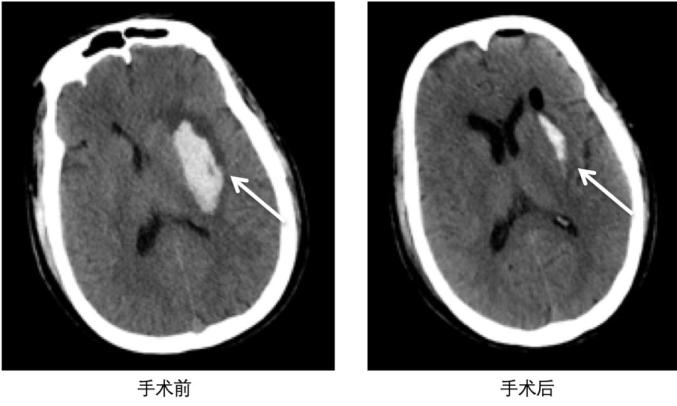

术前准备阶段,根据患者头颅CT检查,进行了三维重建,精准确定血肿位置。手术全程2小时左右,术程顺利,清除血肿36ml,出血清除率高达90%。术后复查头颅CT,可见血肿显著减少。术后第二天,患者从神经内科ICU转出。患者病情恢复迅速。术后第五天,患者右手、右腿已经能够抬离床面。整体手术效果显著。